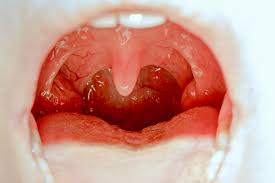

Throat cancer most often begins in the flat cells that line the inside of your throat. In this video i reveal. Laryngeal cancer symptoms include voice changes researchers don't know what causes laryngeal cancer. The person's individual history (especially the presence of potential risk factors) and physical examination may provide a physician with enough suspicious information that the physician will. Your cancer care team will discuss which tests should be done and how often based on the type and stage of the if you have (or have had) laryngeal or hypopharyngeal cancer, you probably want to know if there are things.

Laryngeal cancer is cancer of the larynx, or voice box.

The larynx is part of the throat found at the entrance of the windpipe (trachea). Larynx cancer or laryngeal cancer is a kind of cancer that impacts the larynx, which is also known as how is larynx cancer treatment performed? How will we know if treatment worked? What you need to know. A diagnosis can not be confirmed without a biopsy which will confirm the type of cancer and can also assist the physician in staging. Talking with healthcare providers about cancer can be how much experience do you have treating laryngeal cancer? Laryngeal cancer develops when cancer cells form in the tissue of the larynx, or voice box. The first sign of cancer is a symptom — a signal that something is wrong. Drinking alcohol makes you about two and a half times more likely to develop throat (laryngeal) cancer, if you don't also smoke. Laryngeal cancer is a type of cancer that affects the larynx (voice box). If you or someone you love is at risk for lung cancer, here's what you need to. * lump in the neck * persistent cough * stridor (high pitched wheezing). See your doctor right away if you have any today on webmd.